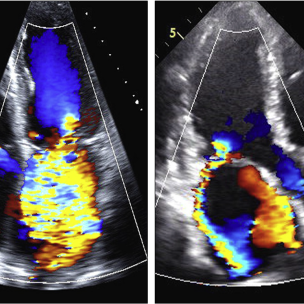

此培训为MAYO诊所推出的心内科fellow系列培训之一,主要目的是能够使大家学习到AMI以后心脏机械并发症的识别和诊断,还有ACS的非心脏的并发症的表现,以及临床中存在与ACS临床上有相似之处的非心脏疾病。 急性心肌梗死后出现的并发症,分为心脏性和非心脏性的,心脏并发症又包括心电学方面的并发症以及机械并发症,非心脏性并发症包括血栓栓塞和出血,还可能出现与心包相关的并发症。 心脏机械并发症包括就是破裂性和非破裂性的2类,破裂性并发症包括游离壁破裂、室间隔穿孔和乳头肌断裂,其中游离壁破裂既可能是直接的穿孔,也可以是亚急性破裂形成假性动脉瘤这样包容性的破裂。而非破裂性机械并发症包括严重的左室心力衰竭,右室梗塞,左室壁动脉瘤以及缺血性二尖瓣反流。 从根本上来说,这些严重并发症的发生都与心脏的泵功能衰竭有关,泵功能的衰竭造成了血流动力学不稳定以及基线的电不稳定性。 第一节:非破裂性机械并发症 非破裂性机械并发症,即严重的左室心力衰竭——心源性休克,右室梗塞,左室壁动脉瘤以及缺血性二尖瓣反流。 1、 心源性休克:在心梗发生时,发生心源性休克的主要原因就是大面积的心肌梗死,那么如果要导致心脏泵功能衰竭,左室心肌质量至少要损失40%以上。其他导致心源性休克的原因还有右室梗塞、心脏破裂以及快速和缓慢性心律失常。 2、 右室梗塞:也是导致心源性休克发生的重要原因。在下壁心梗的患者中,大概有33%的患者同时也发生右室梗死,这种情况多见于RCA近端闭塞,与高死亡风险相关。在所有下壁STEMI者中都要考虑是否同时存在RV梗塞,心电图V1和RV4导联ST段抬高超过1mm为其特异性心电图改变(图1)。 图1. 右室梗塞的心电图表现 3、 右室梗塞为什么会导致患者发生心源性休克呢?从病理生理上讲,右室急性缺血时会致其收缩不良,导致RV每搏输出量和峰压降低,继而是左室前负荷降低,心输出量降低;另一方面,急性缺血还同时使右室舒张功能受损,此时右心充盈压显著增加,并且由于右室急剧扩张,会在心包内占据很大体积,使得心包内压力显著增加,这些综合造成的结果使RV和LV的充盈减少。左心充盈压下降而右心压力不断升高,最终导致低血压、肺血流减少、颈静脉压升高,其临床结果可能类似于心包填塞以及缩窄性心包炎。 4、 左室壁动脉瘤(图2):首先提出一个问题供大家思考,以下有关左室壁动脉瘤的说法哪一个是正确的?1左室壁动脉瘤只局限于心内膜下;2有一个相对狭窄的颈部;3是否都与前壁心梗有关;以及4容易有血栓的附着,并且心包是组成瘤壁的一部分。实际上,左室壁动脉瘤在STEMI后的发生率<5%,前壁梗死的患者更易发生,及时进行再灌注治疗可以降低其发生率。它突出于心腔外侧,瘤壁就是左室壁,颈部和底部的比例大约是1:1,可以出现附壁血栓。所以上述说法中只有3是正确的。 图2. 左室壁动脉瘤示意图,O;颈部,D:底部,LA:左心房,LV:左心室,AO:主动脉 5、 缺血性二尖瓣反流:为心梗后左室重构所致,表现为乳头肌移位、乳头肌功能不良使瓣叶活动受限以及瓣环扩张(图3)。治疗的焦点集中于及时的再灌注治疗、利尿剂的应用和后负荷的降低,如果遗留严重的二尖瓣反流,则会导致心梗后的远期生存率下降。 图3. 瓣环扩张(A)、乳头肌功能不良致瓣叶活动受限(B)导致大量MR 第二节:破裂性机械并发症 破裂性并发症包括游离壁破裂、室间隔穿孔和乳头肌断裂,其中游离壁破裂既可能是直接的穿孔,也可以是亚急性破裂形成假性动脉瘤这样的包容性破裂。大多数破裂性并发症都发生在AMI的第一个24小时之内,剩余的则发生在1周之内。通过超声心动图可以发现MI的机械并发症,包括急性乳头肌断裂、下段室间隔断裂、上段室间隔断裂以及二尖瓣脱垂。 1、 乳头肌断裂所致二尖瓣反流(图4):乳头肌断裂常发生在MI后的2~7天,急性缺血事件发生时,从心外到心内的压力梯度增加,心内灌注降低,乳头肌属于心内结构,缺血的敏感性增加。一旦出现需要外科手术治疗。 图4. 乳头肌断裂(箭头所示) 2、 室间隔缺损(图5):属于MI后的罕见并发症,多于梗死后3~5天发生,在梗死后即刻或者第一个24小时内就可以发生,部分与患者进行的纤溶治疗有关。由于再灌注治疗的开展,目前发生率已经由2%降至0.2%。破裂发生在健康心肌和坏死心肌的交界处,在前壁心梗时,缺损位于室间隔心尖部,下壁心梗时缺损则位于下-后间隔基底段,RV梗死及功能失常者预后不良。 图5. 前壁心梗(A)、下壁心梗(B)所致不同部位室间隔穿孔 3、 游离壁破裂:急剧的、常为致死性机械并发症;发生率<1%;MI后死亡约8~24%是由此而造成;通常在梗死后的5天内发生。好发因素包括1首次心梗,2前壁心梗,3老年患者以及4女性。 4、 亚急性破裂:是一种特殊类型的游离壁破裂,占所有游离壁破裂患者的约1/3,是因为附壁血栓和心包覆盖了穿孔部位所致,局部表现为假性动脉瘤(图6),临床上常比较隐匿,并且可能仅通过UCG发现,因此任何超声发现的心脏周围局部积液都需要引起怀疑并详细扫查。与真性动脉瘤(即左室壁动脉瘤)不同,假性动脉瘤的颈部狭窄,颈部与底部的比值<0.5,心包是瘤壁的组成部分。亚急性破裂的进展常是难以预测,可以进展至完全破裂乃至心包填塞,因此需要外科治疗。 图6. 左室假性动脉瘤示意图,O;颈部,D:底部,LA:左心房,LV:左心室,AO:主动脉 第三节:AMI的非心脏并发症 AMI的非心脏并发症主要包括血栓栓塞和出血,以及心包并发症。那么下面关于左室血栓的说法哪个是正确的呢?1下壁心梗更为常见,2如果不予治疗栓塞风险可达50%,3栓塞的风险取决于血栓的移动性和是否凸出于腔内。左室血栓常(图7)见于大面积前壁心梗,在再灌注前时代其发生率可高达40%,有再灌注治疗后这一几率已降至4~15%;经胸超声心动图是发现LV血栓的第一选择;心脏MRI的敏感性更高,但与超声心动图的特异性相似。由于心梗后不运动和运动障碍的室壁区域存在静止血流,因此如容易在局部形成附壁血栓。如果梗死部位为心尖部,且左室EF值减低达<30%,则存在血栓栓塞的高风险。如果未治疗,左室血栓发生栓塞的风险为10~15%,这一风险的高低还取决于栓子的移动性和是否突出于心腔内,早期且持续的抗凝治疗(3~4个月)可以降低栓塞风险。 图7. 左室心尖部附壁血栓 一图总结心脏机械并发症 第四节:类似ACS的非心脏疾病 通过一个有趣的病例,我们来学习一下在临床中可能存在类似于ACS表现的非心脏疾病。这是一个77岁老年女性,症状为头晕、恶心、呕吐,急诊CT除外了急性卒中,但心肌坏死标记物升高,心电图提示为Af、并且下壁前壁导联T波倒置,但超声心动图上仅表现为室间隔中下段至左室心尖部运动减低,没有看到下壁及前壁的运动异常。随后患者出现严重的高血压和心动过缓,并存在定向力、消化不良和眼球震颤,继续监测头CT及MRI,结果发现枕叶大面积脑梗。实际上,早在1947年,急性卒中所引起的ECG变化就已经被报道,病程中出现深大的倒置T波则被称为神经源性T波。在急性颅内事件发生时可以存在肌钙蛋白的升高以及心电图出现ST-T改变,在卒中的急性期,ECG诊断急性心梗的特异性会降低。 除急性脑血管病以外,以下疾病也会出现类似于ACS的临床发现,包括心电图异常和心肌坏死标记物升高,如特发性应激性心肌病,主动脉夹层,肺栓塞等等,需要及时进行诊断及鉴别诊断。 最后需要强调的是,超声心动图是发现AMI后心脏机械并发症的最重要检查,AMI发生后一周内必须行UCG检查以发现隐匿的高危并发症。